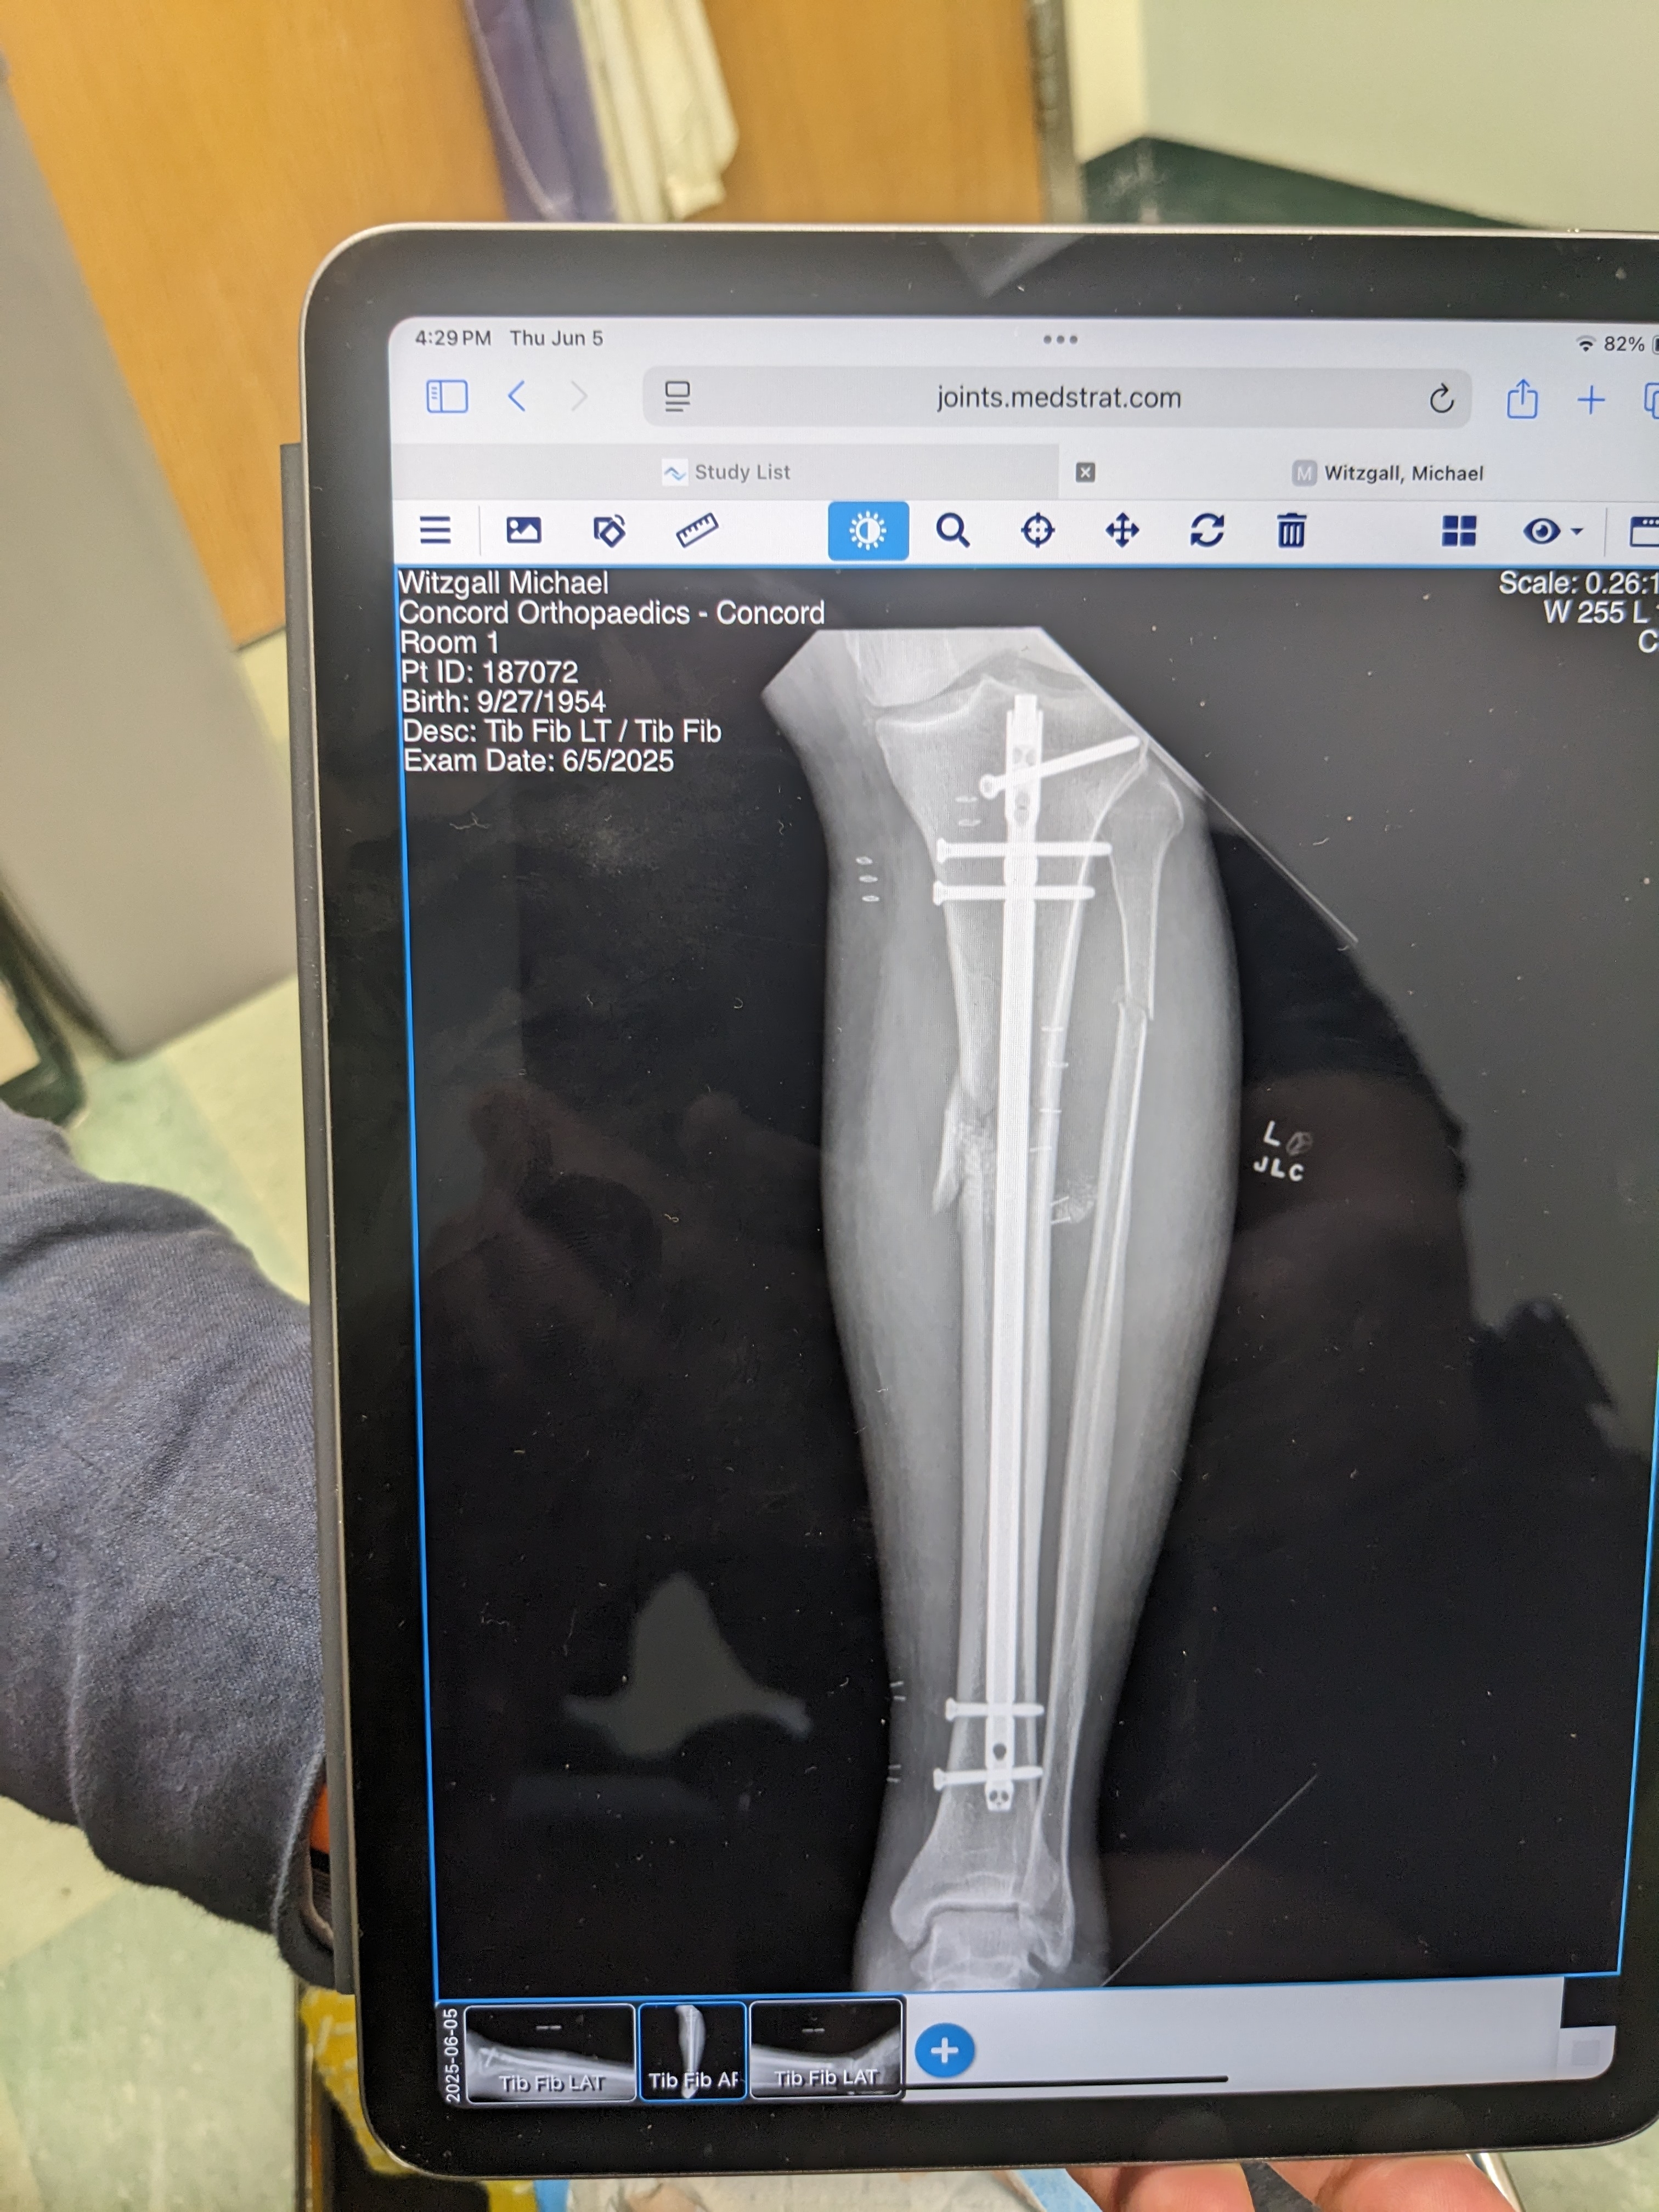

Calf was crushed. Multiple compound fractures bone piercing the bloody flesh.

My platoon of guardian angels prevented my knee and ankle from being destroyed, thus the surgical team was able to install at least a 1/2 pound of titanium to reconstruct what was left of my calf, as there was enough bone left to attach the titanium bones to the joints. I have nerve damage.

I underwent a third operation on my poorly healing bones. Hopefully this much hardware will allow what bones remaining to fuse. My leg is now more stable but traumatized after being opened up again.

Wow. Looks like an Ace Hardware store.

Wow that is a lot of hardware in a small space. Sure hope your recovery continues well and you can get back on your tractor.

New hardware is providing more stability. Now only hope the crunched Tibia begins to mend.